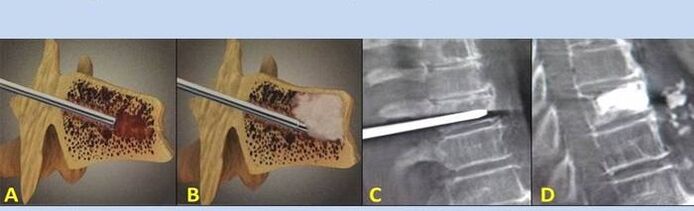

- Πυρηνοπλαστική – Αφαίρεση του πυρήνα του δίσκου. Η επέμβαση ανακουφίζει από την πίεση στις νευρικές απολήξεις.

- Παρακέντηση σπονδυλοπλαστικής – Μέθοδος σταθεροποίησης των σπονδύλων. Κατά τη διάρκεια της διαδικασίας, ο γιατρός γεμίζει τις κοιλότητες της σπονδυλικής στήλης με οστικό τσιμέντο.